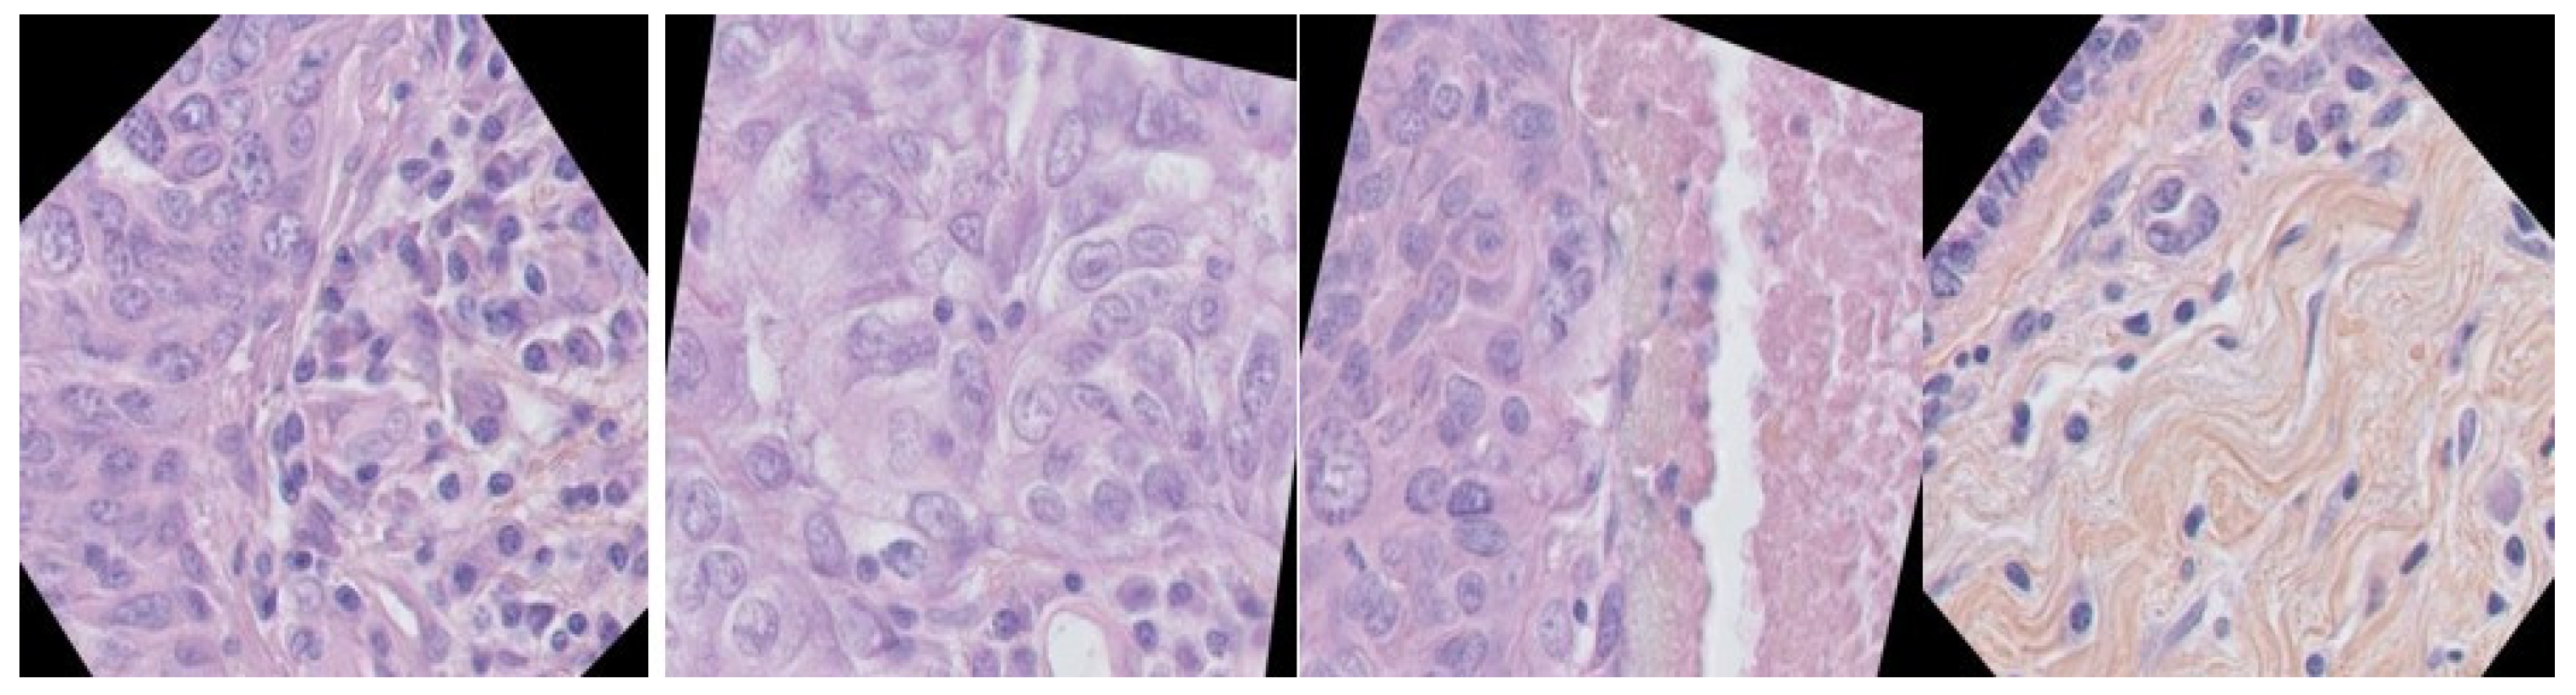

Breast Cancer Histopathological Images Segmentation Using Deep Learning

Experimental Tests